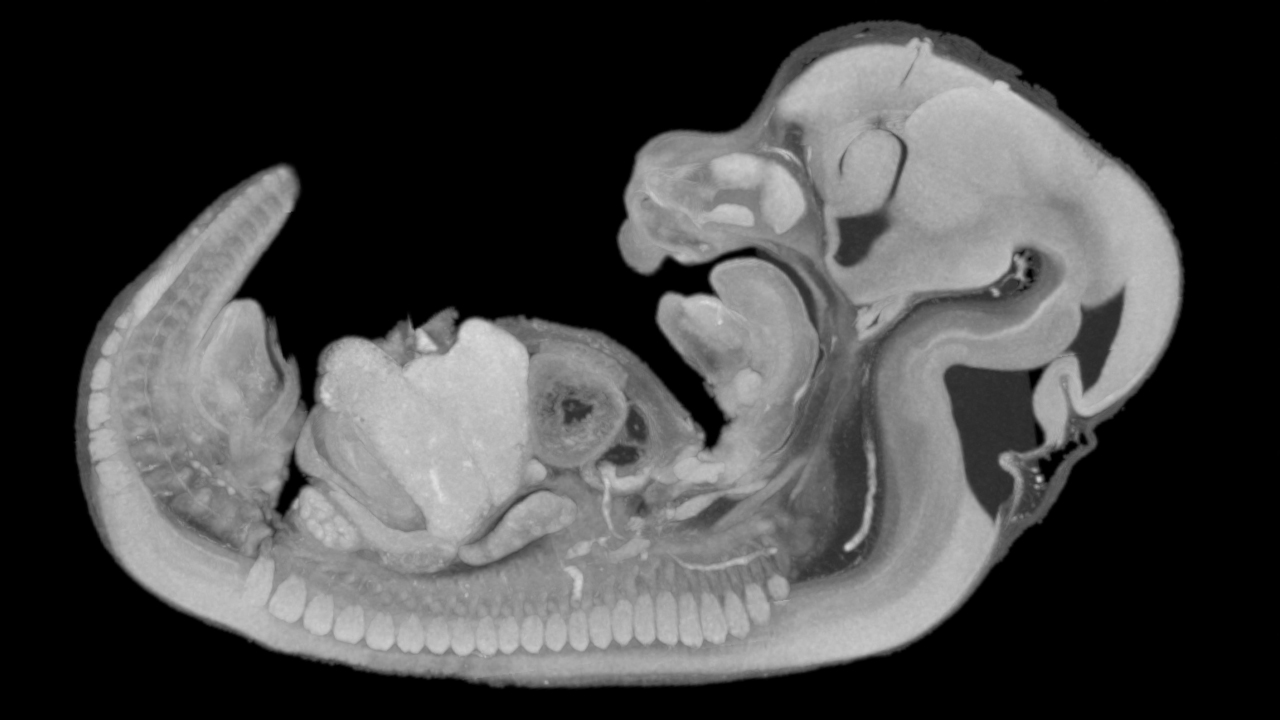

Benchtop MicroCT - Evaluating Mouse Embryos

Mouse embryos are pivotal in biomedical research due to their genetic and physiological similarities to humans. They serve as models for studying developmental processes, genetic disorders, and congenital anomalies.